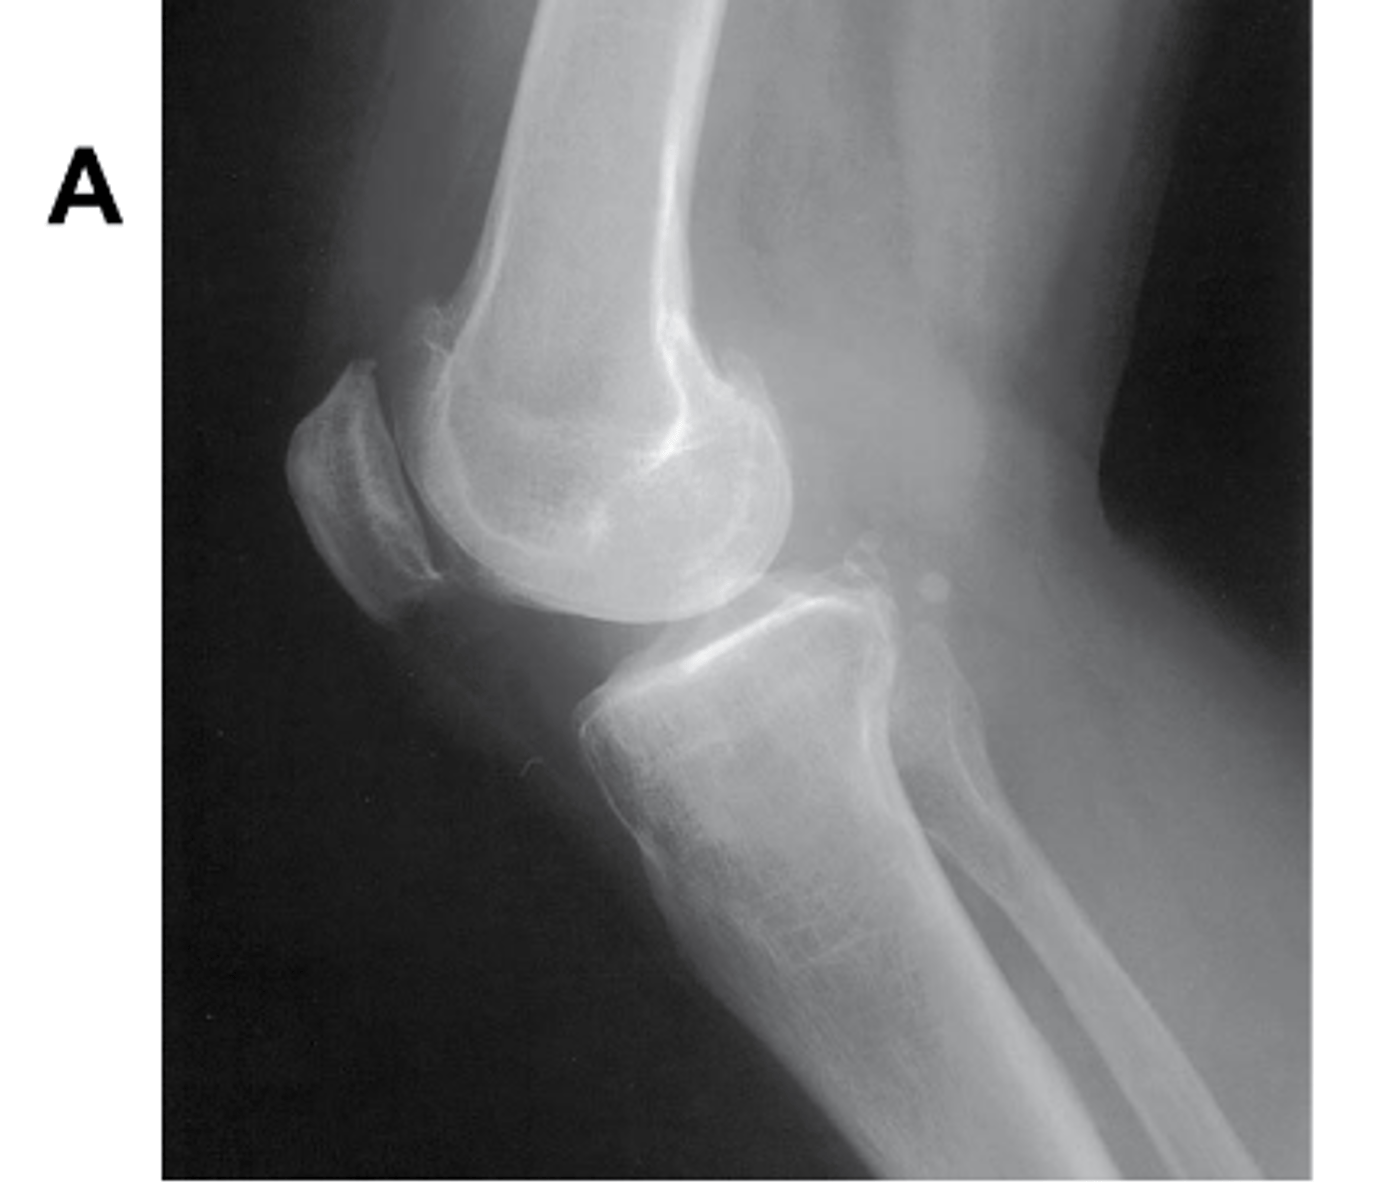

Identify the projection. (Be prepared to identify anatomy and critique for positioning on the quiz)

AP Oblique Knee, lateral rotation

What pathology is visualized on this image?

Osgood-Schlatter disease